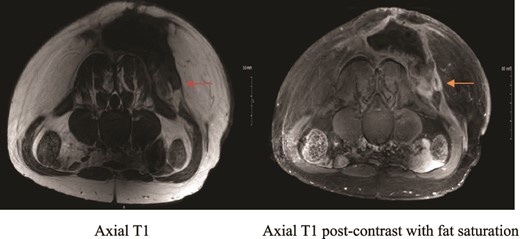

MRI showing suspicious lesion. Postoperative MRI images show re-demonstration of suspicious lesion when correlated to prior MRI from private hospital. The lesion shows low T1 signal intensity (orange arrow), and post-contrast enhancement with central linear area of non-enhancement.